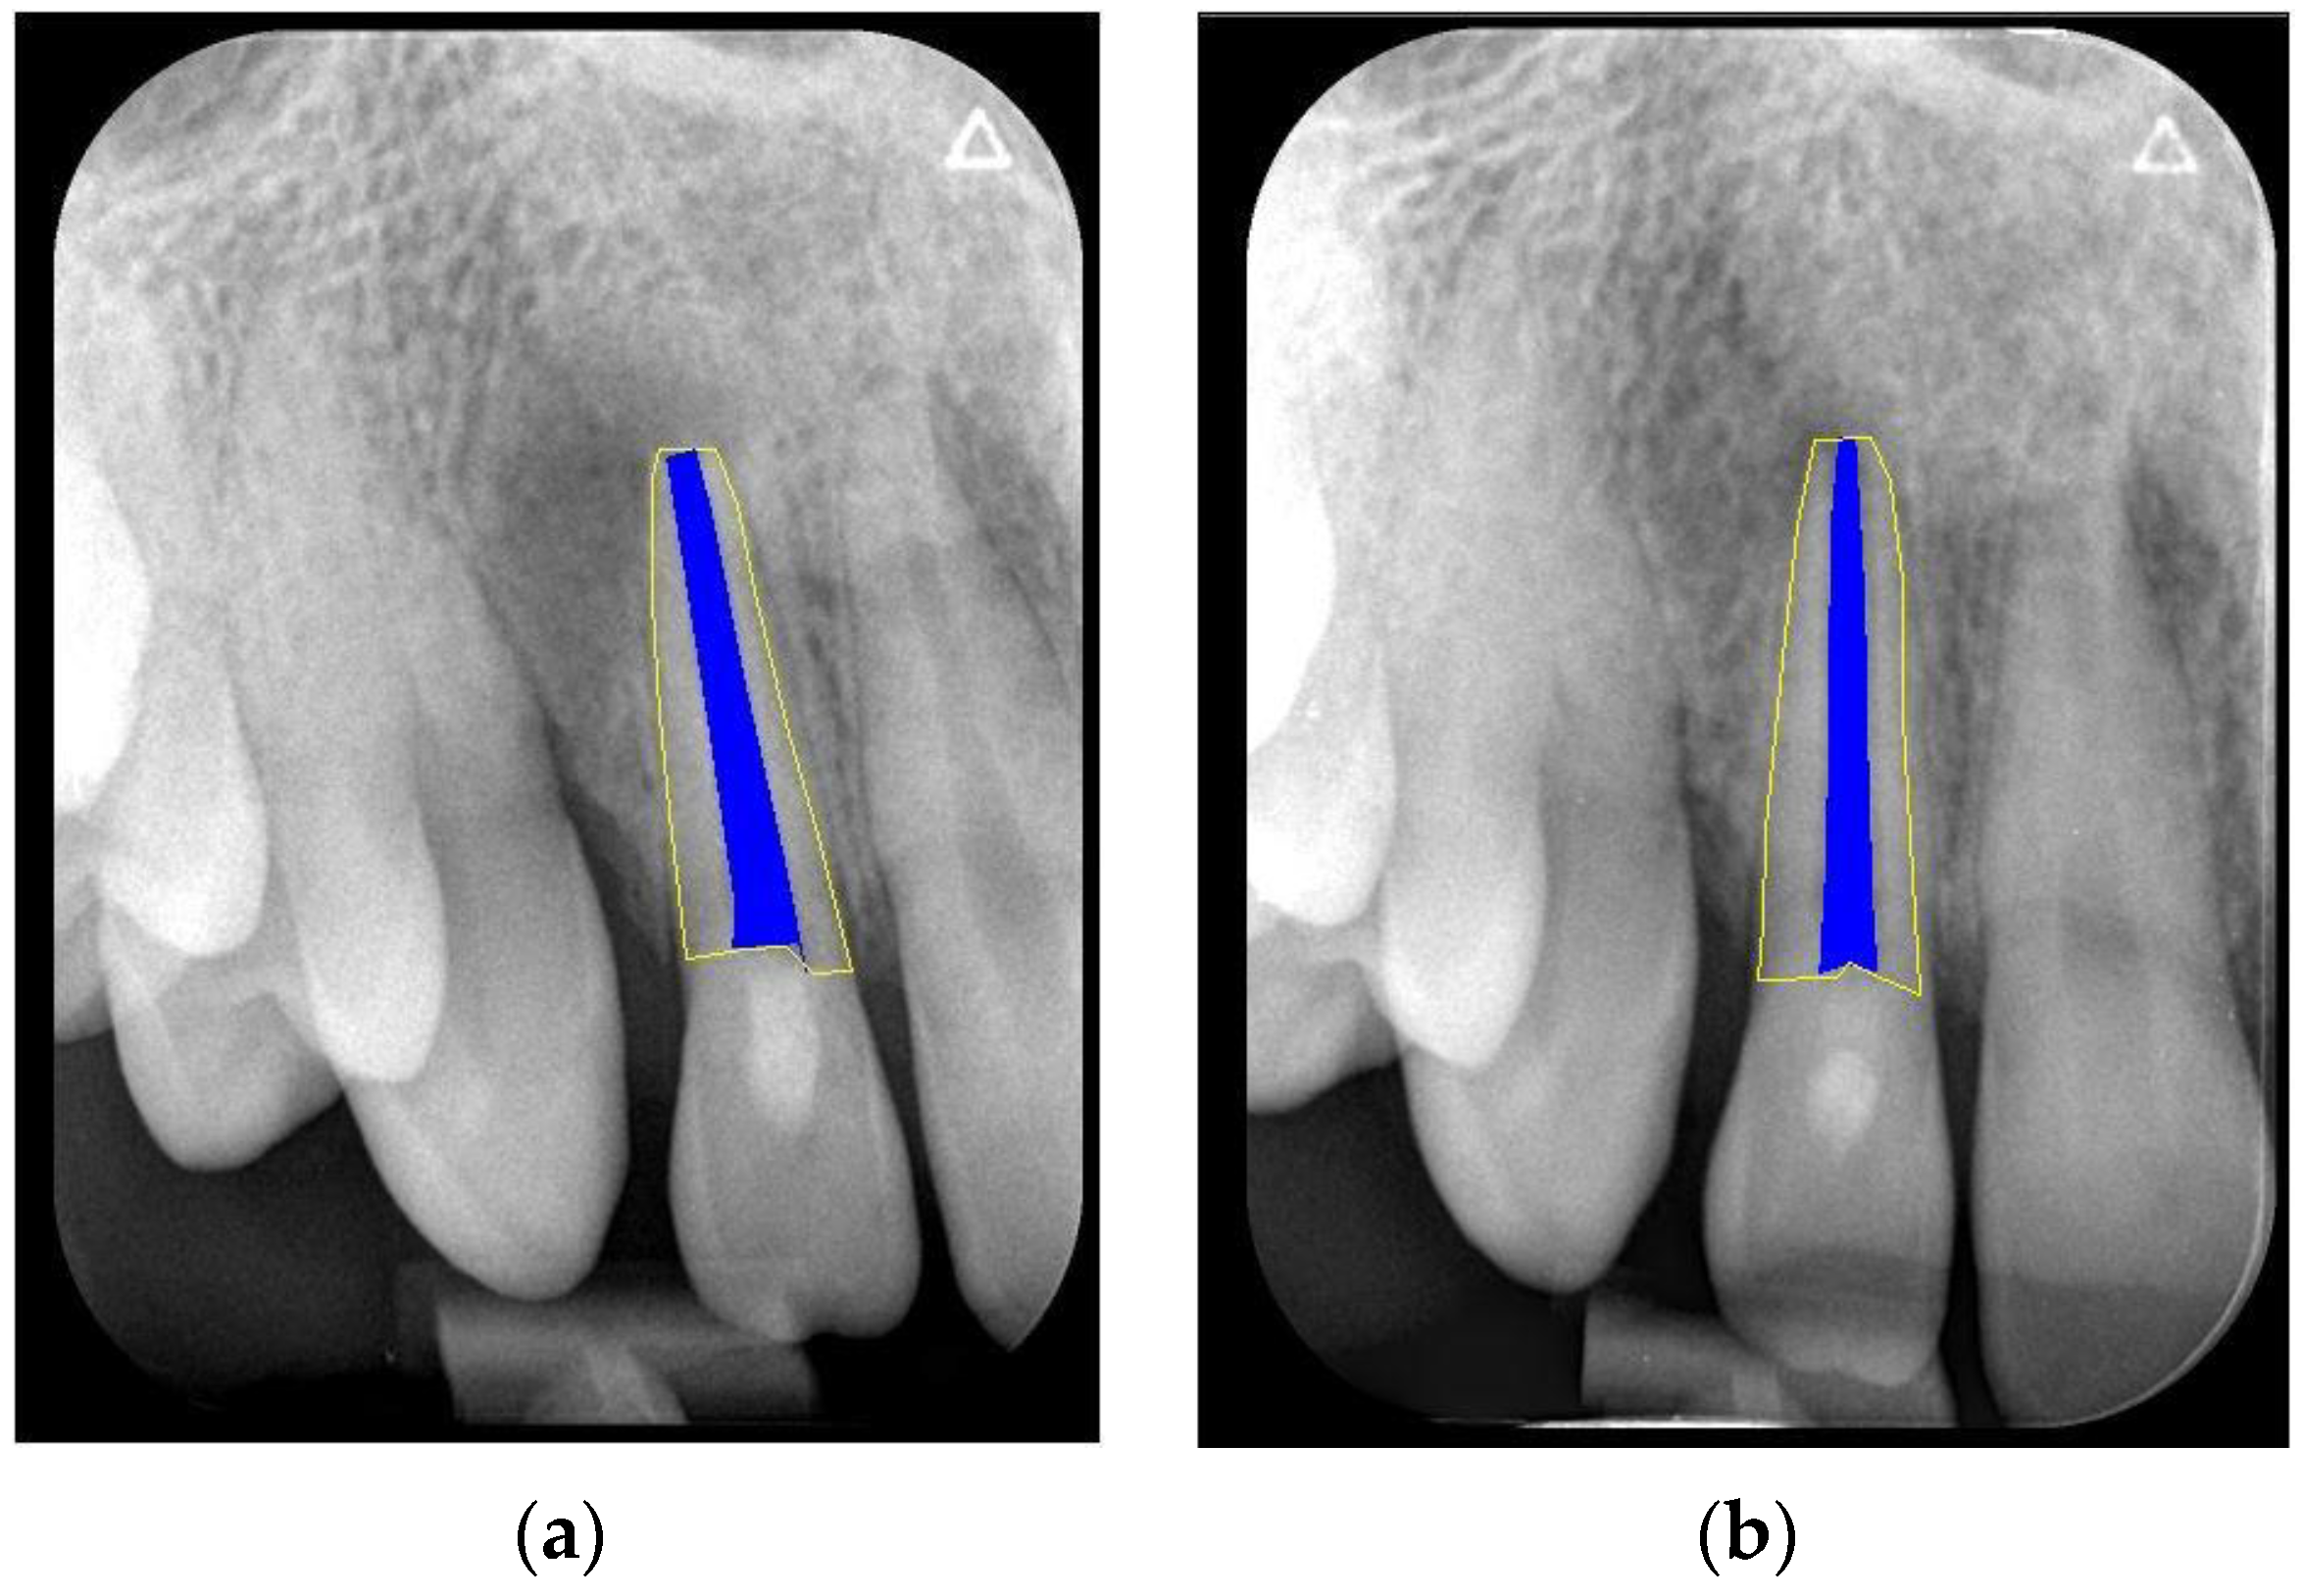

We clinically assessed the outcomes in the absence of any signs and symptoms and a negative cold-sensitivity test. Periapical healing, root elongation, RRA, and apical closure were assessed radiographically (Figure 1a,b). For this, we re-sized the immediate postoperative and follow-up periapical radiographs to match the size and pixels. We used the Freeware Image J software (version 1.47; National Institutes of Health, Bethesda, Rockville, MD, USA) together with the TurboReg plugin tool (Philippe Thevenaz, Biomedical Imaging Group, Swiss Federal Institute of Technology Lausanne, Lausanne, Switzerland) Rasband 1997–2018 [28] as described by Kahler et al. [29]. In brief, for radiographs obtained using different imaging systems, we used the ‘Images to Stack’ and ‘Stack to Images’ functions to equalise the number of pixels in the radiograph. Subsequently, the radiographs of each case were aligned and normalised using the TurboReg plugin tool. This tool enabled the measurement of curved roots (Figure 2a,b). Two evaluators (RY and AYK) conducted the calibration sessions using instructional videos. All cases were separately reviewed by two calibrated examiners. They discussed the case upon obtaining dissimilar results until it was resolved. The above-mentioned changes in root dimension were calculated as a percentage (Figure 3a,b). Hence, we evaluated the effect of the treatment based on the relative increase in RRA and root length.

Figure 1.

Measurement of RRA in an anterior tooth (a) at the end of REP, (b) at the 12-month follow-up. Uncertain healing and an unchanged apical closure are observed.